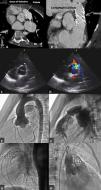

(A and B) Computed tomography showing the aortic end of the iatrogenic fistula near the right coronary ostium and the pulmonary end just proximal to the pulmonary valve; (C and D) transthoracic echocardiogram, parasternal long- and short-axis views of the iatrogenic fistula (*) between the aortic arch and the right ventricular outflow tract (RVOT); (E and F) aortic and conduit angiographies before percutaneous pulmonary valve implantation (PPVI); (G) conduit angiography after pre-stenting and after PPVI; (H) aortic angiography showing opacification of the RVOT.

Case reportA 11-year-old girl, born with tetralogy of Fallot with absent pulmonary valve, underwent surgical repair at three years old with a 15-mm homograft. A small residual ventricular septal defect (VSD) was noted on follow-up. At five years old, calcification and stenosis of the homograft prompted successful balloon angioplasty, and at 10 years old she underwent PPVI under general anesthesia. Coronary contraindications were excluded with an aortic root angiography simultaneous with a fully inflated 20-mm Atlas Gold balloon (Bard Peripheral Vascular Inc, Tempe, AZ) (Figure 1E and F). Pre-stenting was performed with a 43-mm AndraStent XL (Andramed, Reutlingen, Germany) mounted on a 20-mm BiB catheter (Numed Inc, Hopkinton, NY), and a 22-mm Melody transcatheter pulmonary valve (Medtronic Inc, Mounds View, MN) was implanted with an Ensemble delivery system (Figure 1G). The final PA pressure was 28/11/16 mmHg, right ventricular (RV) pressure was 28/8 mmHg, aortic pressure was 77/45/60 mmHg and there was no RV-PA gradient. The exit angiogram excluded an aneurysm of the conduit but no aortic root angiography was performed. On the next day, auscultation revealed a grade 3/6 to-and-fro murmur on the left sternal border. The echocardiogram showed appropriate pulmonary valve function and a diastolic color Doppler jet into the RVOT (Figure 1C and D), which was thought to terminate immediately below the Melody valve and was interpreted as the previously described VSD. Despite this, a normally functioning aortic valve and diastolic flow in the ascending aorta (AA) were documented. As the patient remained asymptomatic she was discharged home.

During follow-up, the patient began to suffer from fatigue on moderate exertion. Transesophageal echocardiography and cardiac catheterization (Figure 1H and Video 1) showed a significant fistula between the AA and the RVOT with Qp:Qs of 2.1:1. Computed tomography (Figure 1A and B) further detailed the anatomy, with the aortic end of the fistula near the right coronary ostium and the pulmonary end just proximal to the valve. The patient underwent surgical repair of the communication with a direct double suture. Intraoperatively, a circular defect was found in the right sinus of Valsalva, 6 mm below the right coronary ostium and above the aortic annulus, with a diameter of 8 mm. The fistula opened in the RVOT in close proximity to the proximal end of the Melody valve. Six months later, the patient is asymptomatic and there is no evidence of the fistula on the echocardiogram. A small residual restrictive VSD (gradient 80 mmHg) has been documented since the postoperative period of the primary surgery.